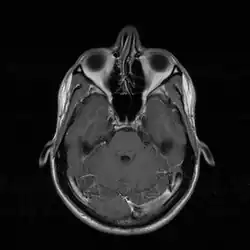

Die Diagnose einer Septumdeviation wird mittels äußerer Inspektion der Nase, vorderer Rhinoskopie, Endoskopie oder Computertomografie (CT) gestellt. Wie stark eine Septumdeviation die Nasenatmung behindert, kann mithilfe einer Rhinomanometrie gemessen werden. Außerdem sollte eine Riechprüfung durchgeführt werden.